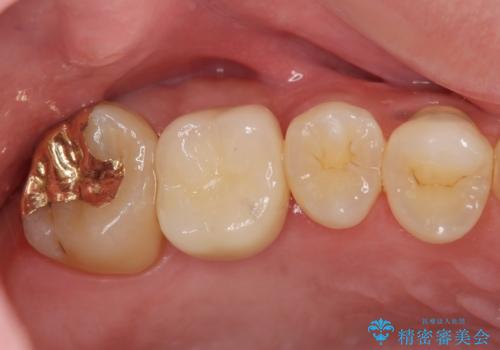

ソケットリフトを伴うインプラント補綴

- 50万円(ストローマンインプラント・ソケットリフト・ジルコニアカスタムアバットメント・ジルコニアクラウン)費用は治療当時の料金となります